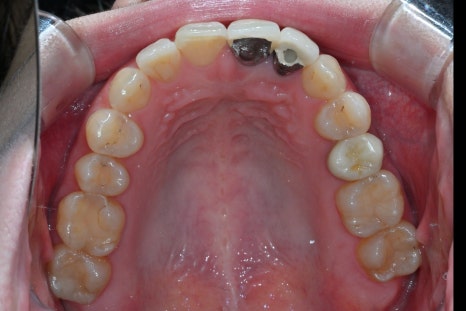

치료 전, 후 비교

<BEFORE>

초진 내원 당시

환자분은 기존 크라운이 변색되고

잇몸과의 경계도 자연스럽지 않아

일상적인 대화나 사진 촬영에서

항상 신경을 쓰고 있었던 상태였습니다.